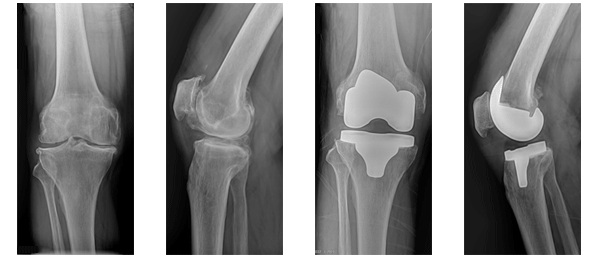

¹«¸ °üÀý(½½°üÀý)

°üÀýÀÌ °üÀý¿°À̳ª ƯÁ¤ Áúȯ ¶Ç´Â ¿Ü»ó µîÀÇ ¿øÀÎÀ¸·Î °üÀý ±â´ÉÀ» ÀÒ°Ô µÇ¸é Àΰø ±Ý¼Ó¹°°ú ÇÃ¶ó½ºÆ½À¸·Î ¸¸µé¾îÁø Àΰø°üÀýÀ» »ðÀÔÇÏ¿© °üÀýÀÇ ¿îµ¿±â´ÉÀ» ȸº¹½ÃŰ¸é¼ ÅëÁõÀ» ¾ø¾Ö°í µ¿½Ã¿¡ º¯ÇüÀ» ±³Á¤ÇÏ¿© ÀÏ»óÀûÀÎ »ýȰÀÌ °¡´ÉÇÏ°Ô ÇÏ´Â ¼ö¼úÀÔ´Ï´Ù.